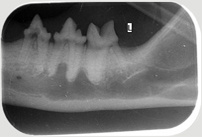

Neben der allgemeinen Untersuchung und der Untersuchung der Zahntaschen mittels Parodontalsonde sind ZAHNRÖNTGEN unumgänglich für eine komplette Diagnostik von Parodontalerkrankungen und bei Zahnresorptionen vor allem bei der Katze (FORL). Dabei werden spezielle Techniken mit Dentalfilmen wie beim Menschen verwendet.

In der Kleintier-Ordination Mittertreffling wird eine moderne digitale Entwicklung verwendet, die die Strahlenbelastung für Ihr Tier verringert. Ohne Zahnröntgen wird das Ausmaß des Knochenverlustes oft unterschätzt und bei der Katze viele Zahnresorptionen übersehen oder unterschätzt. Zudem ist bei einer wie in der Tier-Zahnheilkunde in einer Sitzung durchgeführten Wurzelbehandlung (Endodontie) eine Kontrolle durch Zahnröntgen unbedingt notwendig. Selbst Tumoren können sehr gut erkannt werden und auch die Kontrolle einer Zahnbewegung (Orthodontie) sollte durch Zahnröntgen erfolgen.

Katze mit hochgradiger RL Tumor im Unterkiefer Intraorales Zahnröntgen bei Tumor im Unterkiefer